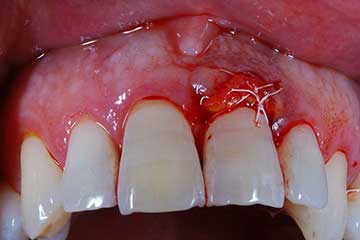

Lembo libero per correggere una recessione gengivale